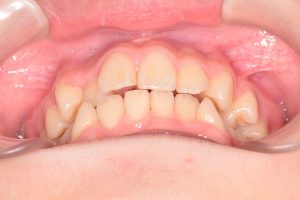

この患者さんは、初診時12才女性。

「上の前歯の中心がずれている」

「全体的に歯並びが良くないのが気になる」

ということで来院されました。

1期治療開始時(2024年3月)

2期治療開始時(2024年11月)

保定開始時(2025年1月)の写真です。

正面

すでに乳歯は1本もありませんでしたが

12歳とまだ若く

骨格的な歯列弓の拡大が期待できること